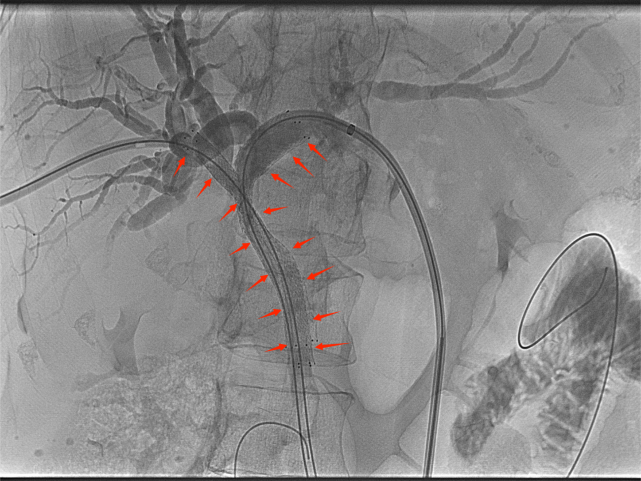

胆道支架置入能很好地弥补经皮肝穿刺胆道引流术的不足之处,通过在胆管狭窄/阻塞处安置金属支架,解除胆道梗阻、恢复通畅,促进胆汁入肠,改善消化功能的同时无需长期带管,显著提高了生活质量,适合短期内有效解除胆道梗阻的患者(如恶性胆道梗阻)。

高位胆道梗阻支架置入